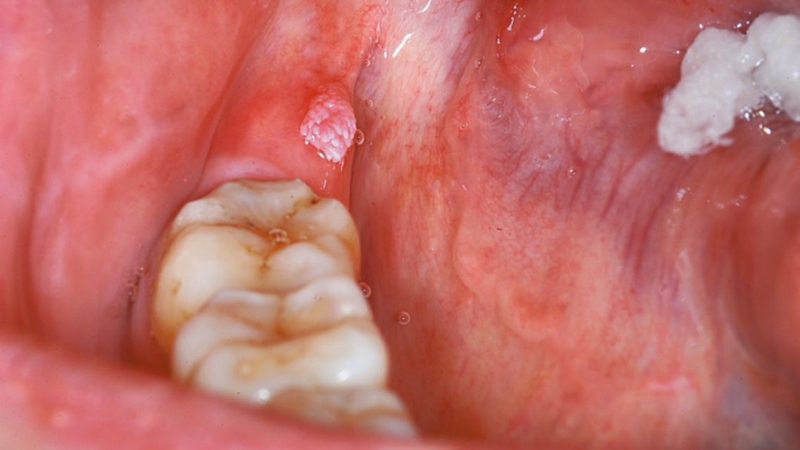

Có thể nhận biết sớm sùi mào gà ở nướu răng qua những dấu hiệu sau:

Sùi mào gà ở nướu răng tuy không gây đau cấp tính nhưng ẩn chứa nhiều nguy cơ nếu không được phát hiện và điều trị kịp thời. Ban đầu, các tổn thương u nhú có thể xuất hiện nhỏ lẻ và ít gây khó chịu. Tuy nhiên, nếu để kéo dài, chúng có xu hướng lan rộng nhanh, liên kết thành cụm lớn, gây chảy máu, nhiễm trùng và rất khó kiểm soát.

Đặc biệt, virus HPV gây sùi mào gà có khả năng lây lan sang các vùng lân cận trong khoang miệng như lưỡi, amidan, niêm mạc má. Trong một số trường hợp hiếm, HPV từ khoang miệng có thể lây xuống đường hô hấp nếu không được ngăn chặn sớm.